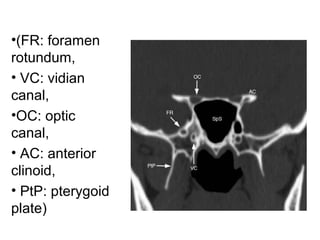

•(FR: foramen

rotundum,

• VC: vidian

canal,

•OC: optic

• AC: anterior

clinoid,

• PtP: pterygoid

plate)

•(FR: foramen rotundum, • VC:vidian canal, •OC: optic canal, • AC: anterior clinoid, • PtP: pterygoid plate)